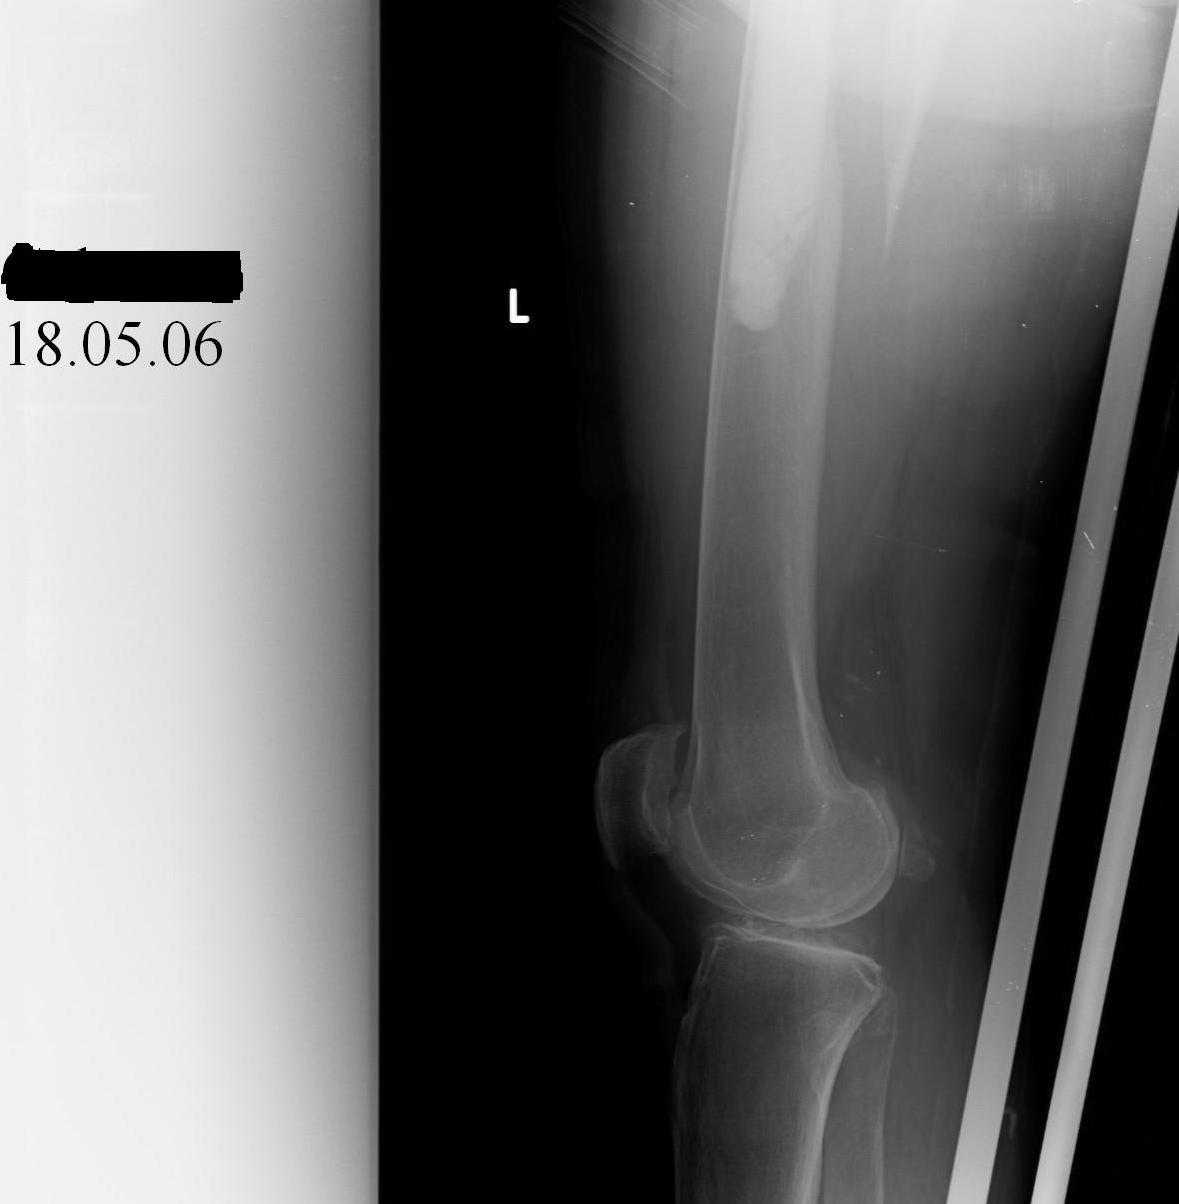

Although, there is just one view, it seems that cement is still holding well on lateral side, cup also seems to be stable, but inside is asymmetric – poly is damaged ... options:

the proximal portion of the stem looks stable. I would consider a long trochanteric plate (synthes) with cables and unicortical locking screws along stem and bicortical screws below. allograft strut probably not necessary. no cables around the fragments. or, a left supracondylar femur plate could be reversed and placed along greater trochanter and fixed to the bone as above. good case.

Мое мнение,что бедренный компонент эндопротеза нестабилен - медиальный кортикал бедренной кости полностью отделился от цементной мантии эндопротеза, нет уверенности в том, что цементная мантия бедренного компонента цела на всем протяжении, чаще, она подвергется растрескиванию, особенно при таком высокоэенергетическом переломе. Мое мнение, вданном случае показано ревизионное эндопротезирование с заменой бедренного компонента на ревизионноу ножку. Стабильность вертлужного компонента оценить трудно на данном снимке, но по моему она стабильна. Но я бы проверил это интраоперационного и взял бы на операцию и вертлужный компонент.

Although femoral stem seems stable, its cement mantle is completely destroyed and devoid of bone medially and distally (where its most necessary)

the cement mantle looks good in the whole mataphyseal region so I'll consider it a Vancouver B1 fracture, so ORIF.